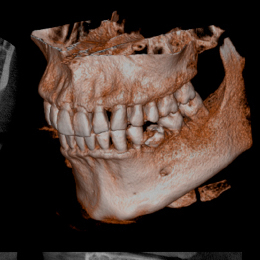

従来のX線と比べると

2次元の平面的な画像でしたが、CTでは3次元の立体的な画像で診断ができるため、骨の形や密度、神経の走行状態、また歯の根の先の病巣の位置や大きさなどが正確に把握できるようになりました。

これは安全性の高い治療につながります。